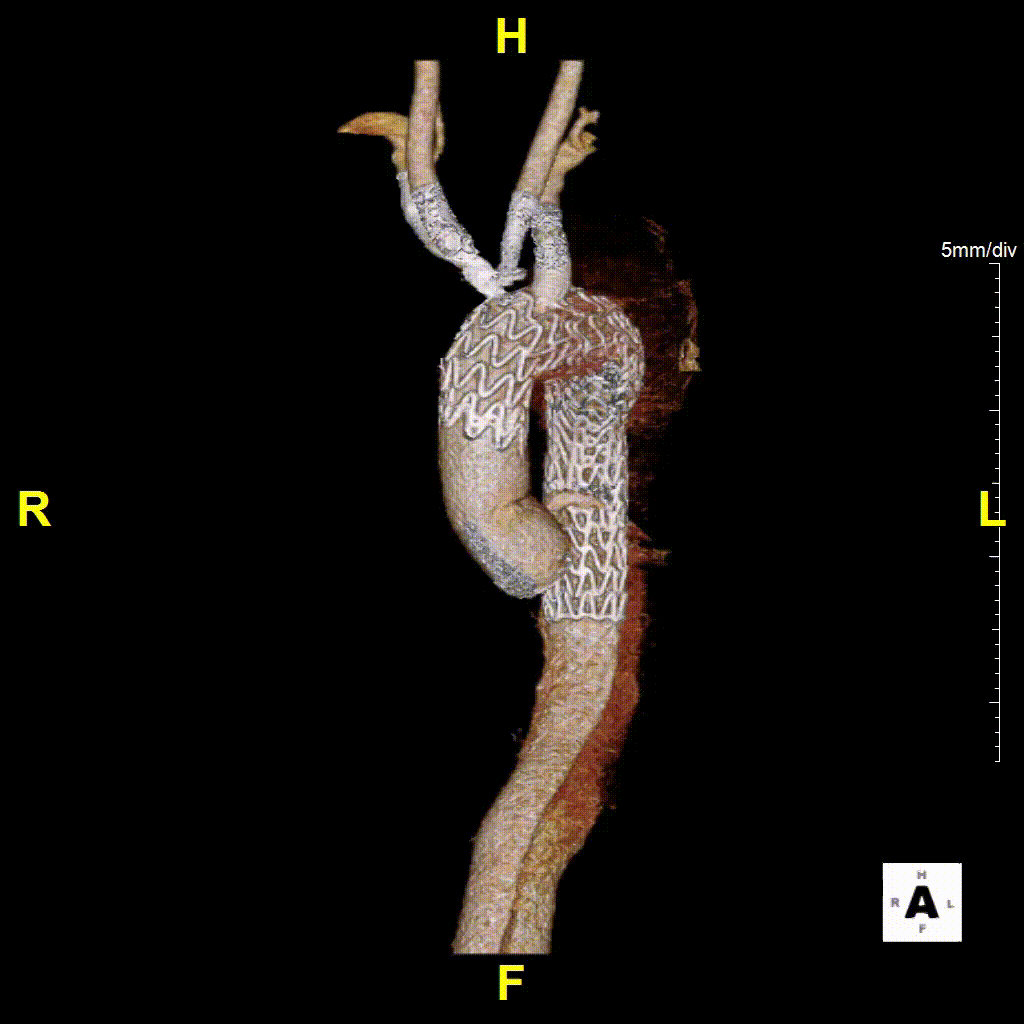

② 八爪鱼支架(多分支支架)的应用

用于内脏区全腔内重建,该技术顺应血流方向,不改变血流动力学,中期疗效确切。

特殊处理:腹腔干可栓塞。

注意:避免倒置操作,减少血栓形成风险。